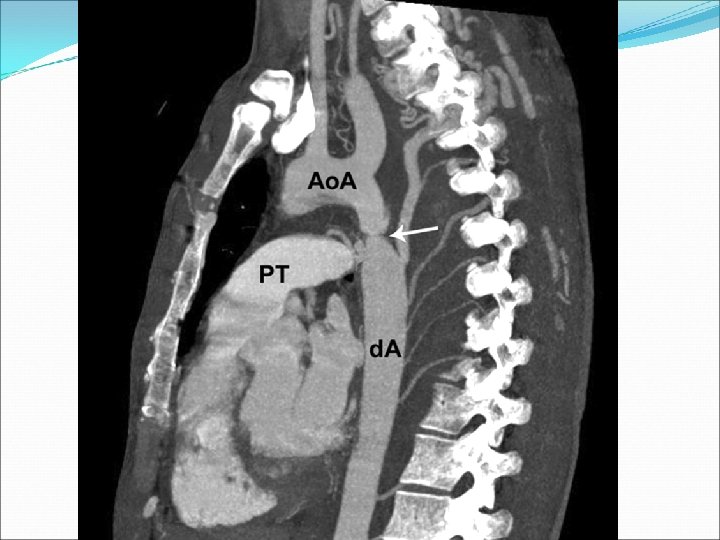

Beş yaşında bir çocuk egzersiz sonrası olan bacak ağrıları yakınmaları ile getiriliyor. Fizik muayenede kan basıncı 130/85 mm. Hg olarak bulunuyor ve femoral nabızlar zayıf alınıyor. Bu çocuk için en olası tanı aşağıdakilerden hangisidir? A) Atrial septal defekt B) Patent duktus arteriozus C) Fallot tetralojisi D) Aort koarktasyonu E) Pulmoner stenoz